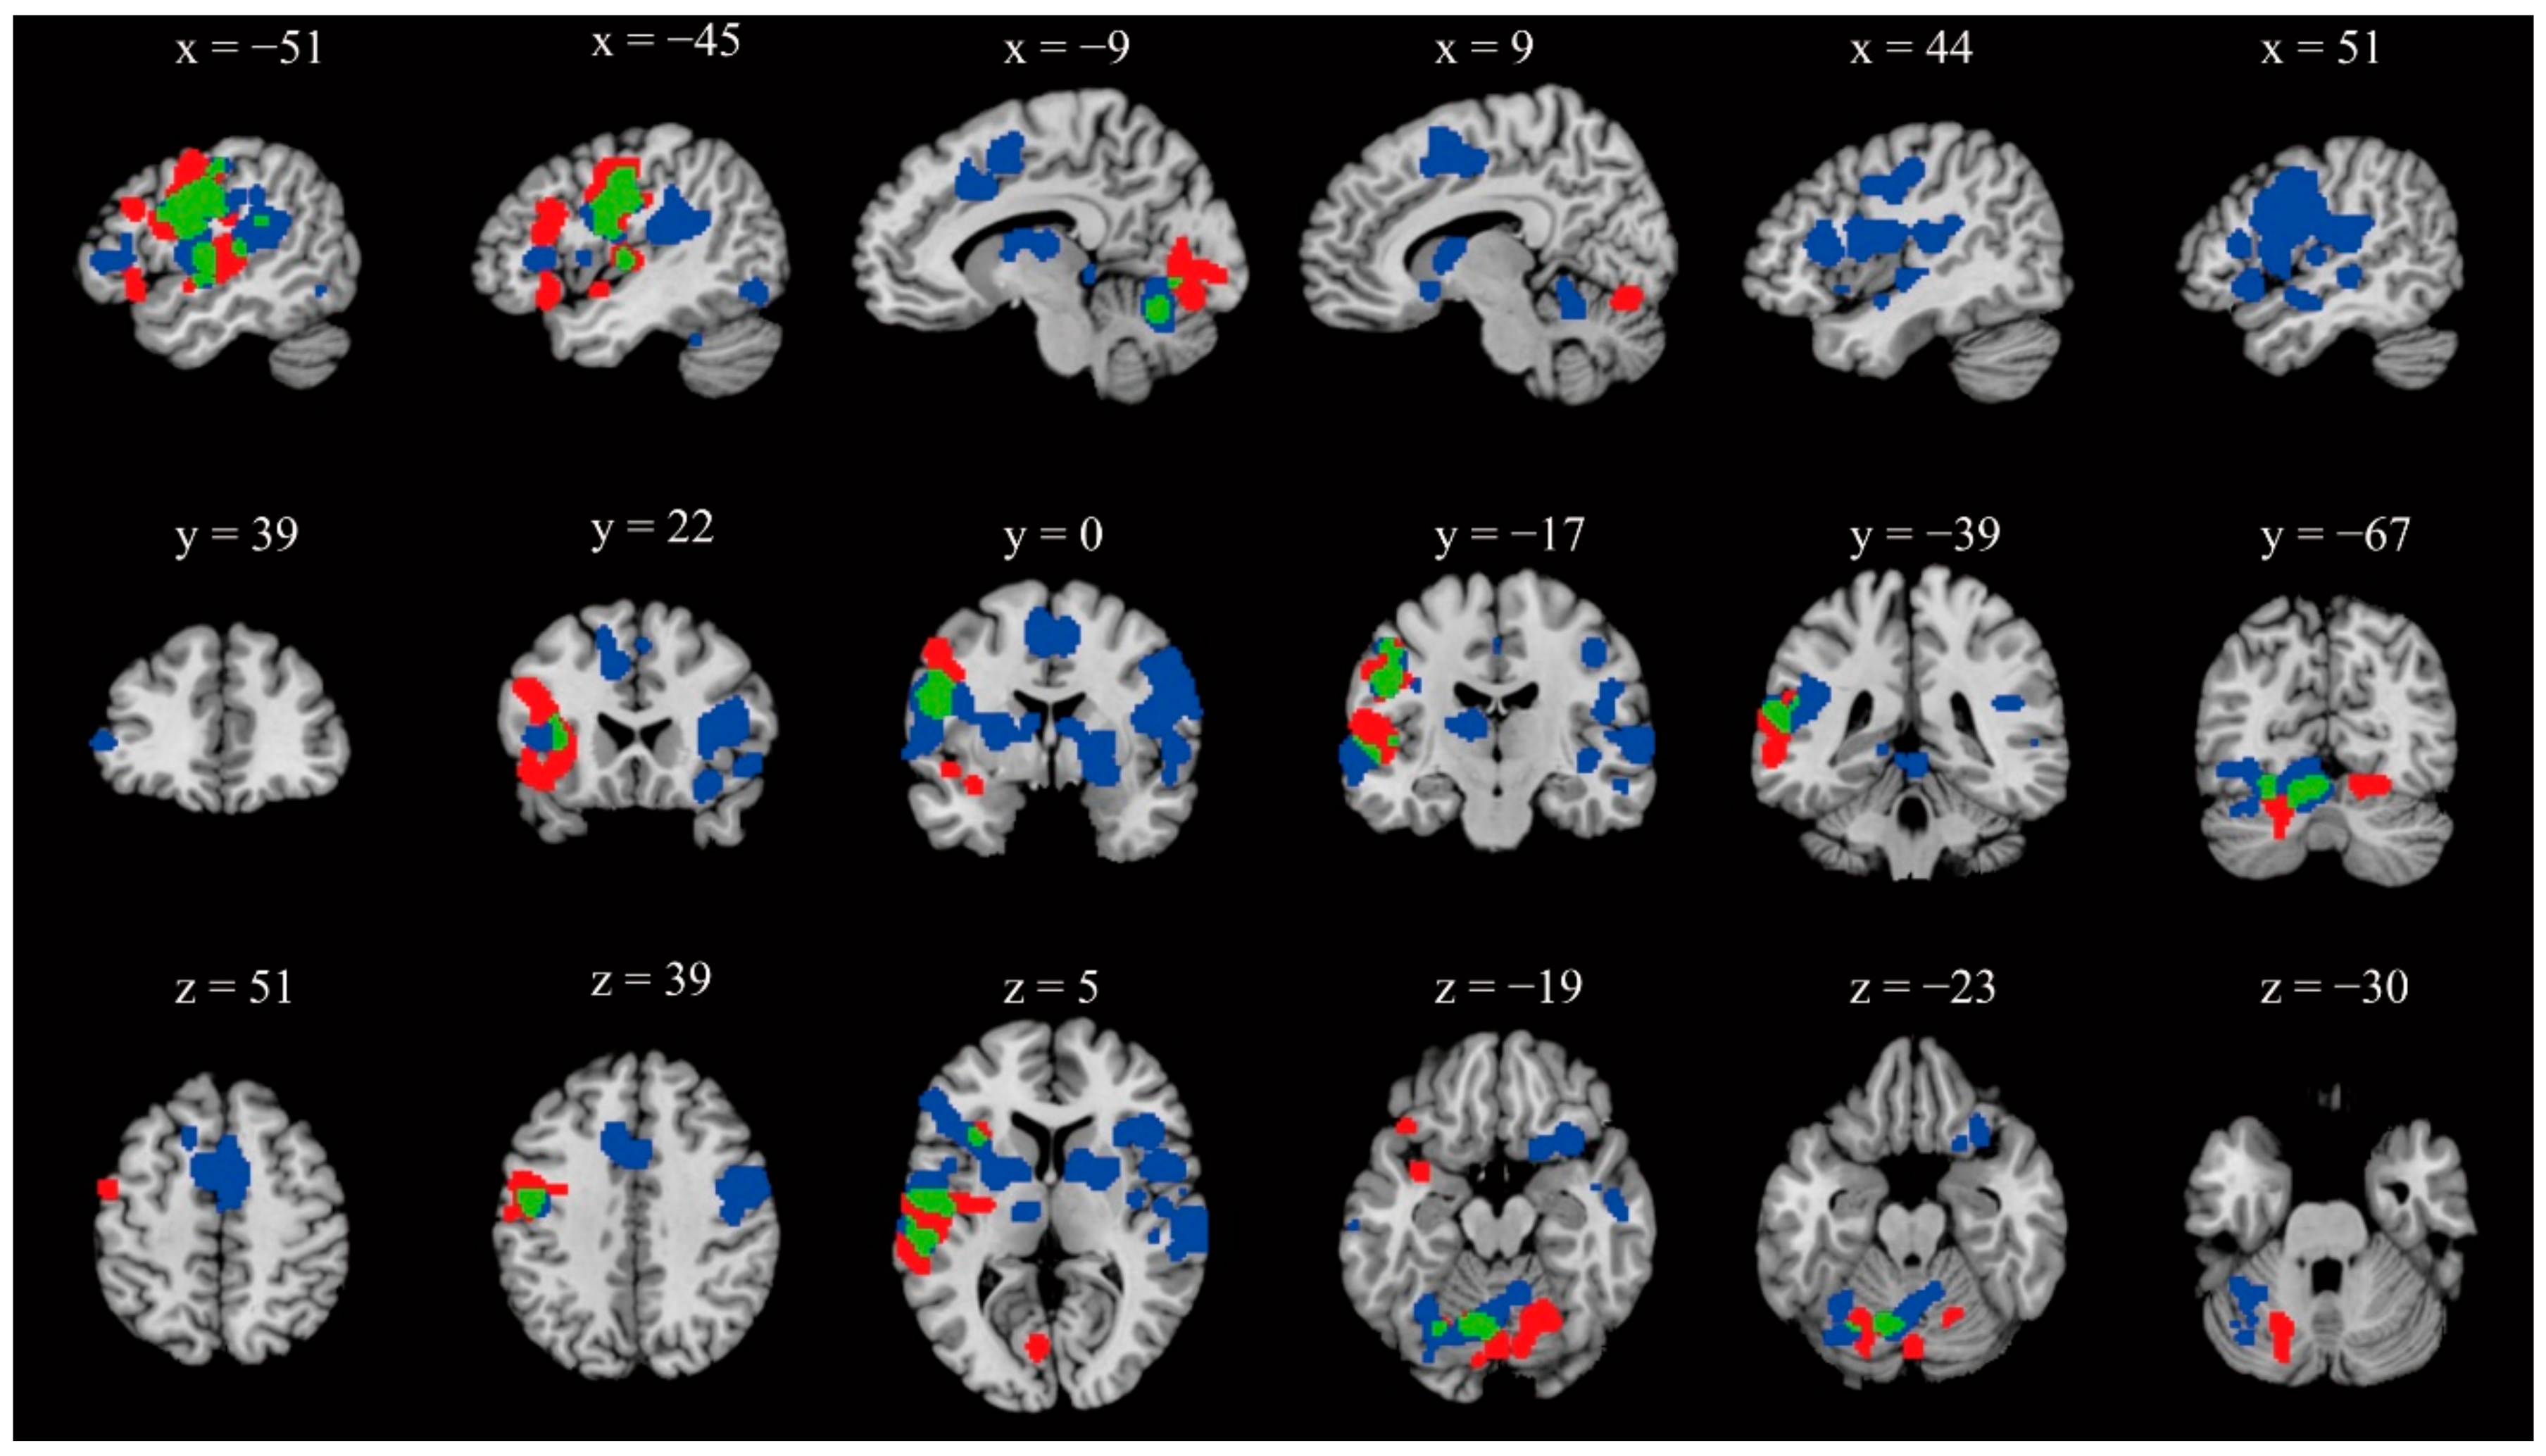

| Cluster | Volume (mm3) | Weighted Center (X,Y,Z) | Maximum ALE Value (X,Y,Z) | ALE Value (10−2) | Anatomical Label | BA |

|---|---|---|---|---|---|---|

| 1 | 47,408 | 46.1, −2.5, 10.2 | 56, −2, 28 | 2.70 | R Postcentral Gyrus | 6 |

| 46,22,10 | 1.95 | R Inferior Frontal Gyrus | 45 | |||

| 60, −6, −2 | 1.92 | R Superior Temporal Gyrus | 22 | |||

| 50, 6, 8 | 1.79 | R Precentral Gyrus | 44 | |||

| 20, −2, −2 | 1.65 | R Globus Pallidus | / | |||

| 46, −26, 12 | 1.55 | R Transverse Temporal Gyrus | 41 | |||

| 42, −6, 14 | 1.54 | R Insula | 13 | |||

| 18, 12, −14 | 1.76 | R Putamen | / | |||

| 66, −2, 20 | 1.51 | R Precentral Gyrus | 4 | |||

| 14, 8, 2 | 1.38 | R Caudate | / | |||

| 42, −14, −6 | 1.38 | R Claustrum | / | |||

| 50, 16, −10 | 1.23 | R Inferior Frontal Gyrus | 47 | |||

| 44, −18, 44 | 1.22 | R Postcentral Gyrus | 3 | |||

| 54, −4, −14 | 0.94 | R Superior Temporal Gyrus | 38 | |||

| 56, −32, 0 | 0.94 | R Middle Temporal Gyrus | 21 | |||

| 58, −30, 32 | 0.83 | R Inferior Parietal Lobule | 40 | |||

| 2 | 36,528 | −46.8, −9.2, 15 | −52, −8, 30 | 2.53 | L Precentral Gyrus | 6 |

| −56, −4, 20 | 1.73 | L Precentral Gyrus | 4 | |||

| −24, 2, 6 | 1.62 | L Putamen | / | |||

| −66, −20, −2 | 1.56 | L Superior Temporal Gyrus | 22 | |||

| −48, −42, 20 | 1.43 | L Superior Temporal Gyrus | 13 | |||

| −38, 20, 4 | 1.43 | L Insula | 13 | |||

| −12, −16, 10 | 1.41 | L Thalamus | / | |||

| −58, −32, 12 | 1.37 | L Superior Temporal Gyrus | 42 | |||

| −46, 26, 4 | 1.32 | L Inferior Frontal Gyrus | 13 | |||

| −52, 36, 2 | 1.23 | L Inferior Frontal Gyrus | 46 | |||

| −56, 8, 24 | 0.99 | L Inferior Frontal Gyrus | 9 | |||

| −52, −16, 46 | 0.84 | L Postcentral Gyrus | 2 | |||

| −50, −26, 32 | 0.83 | L Inferior Parietal Lobule | 40 | |||

| −58, −48, 22 | 0.77 | L Supramarginal Gyrus | 40 | |||

| −50, 24, 14 | 0.70 | L Inferior Frontal Gyrus | 45 | |||

| 3 | 11,744 | −0.2, 6.2, 48.8 | −6, 4, 52 | 2.02 | L Medial Frontal Gyrus | 6 |

| 0,4, 48 | 1.76 | L Cingulate Gyrus | 24 | |||

| 6, 4, 50 | 1.59 | R Medial Frontal Gyrus | 6 | |||

| 6, −8, 48 | 1.05 | R Paracentral Lobule | 31 | |||

| −14, 20, 48 | 0.93 | L Superior Frontal Gyrus | 6 | |||

| 0, −14, 48 | 0.77 | R Paracentral Lobule | 31 | |||

| 4 | 11,664 | −16.9, −61.7, −17.6 | −6, −66, −18 | 2.00 | L Cerebellum Declive | / |

| 2, −38, −8 | 1.20 | L Cerebellum Culmen | / | |||

| −36, −72, −26 | 1.18 | L Cerebellum Uvula | / | |||

| 10, −52, −18 | 1.16 | R Cerebellum Culmen | / | |||

| −44, −72, −12 | 1.05 | L Fusiform Gyrus | 19 | |||

| 8, −48, −10 | 0.89 | R Cerebellum Cerebellar Lingual | / | |||

| −14, −36, 0 | 0.85 | L Parahippocampal Gyrus | 27 |